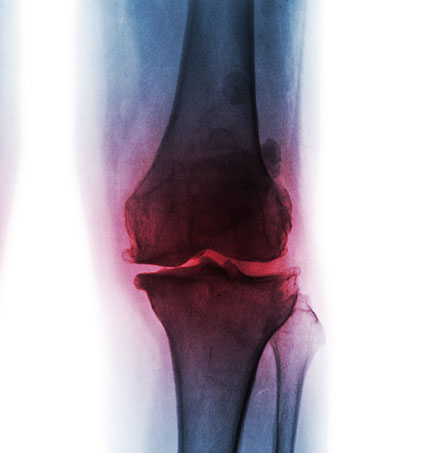

knee x-ray